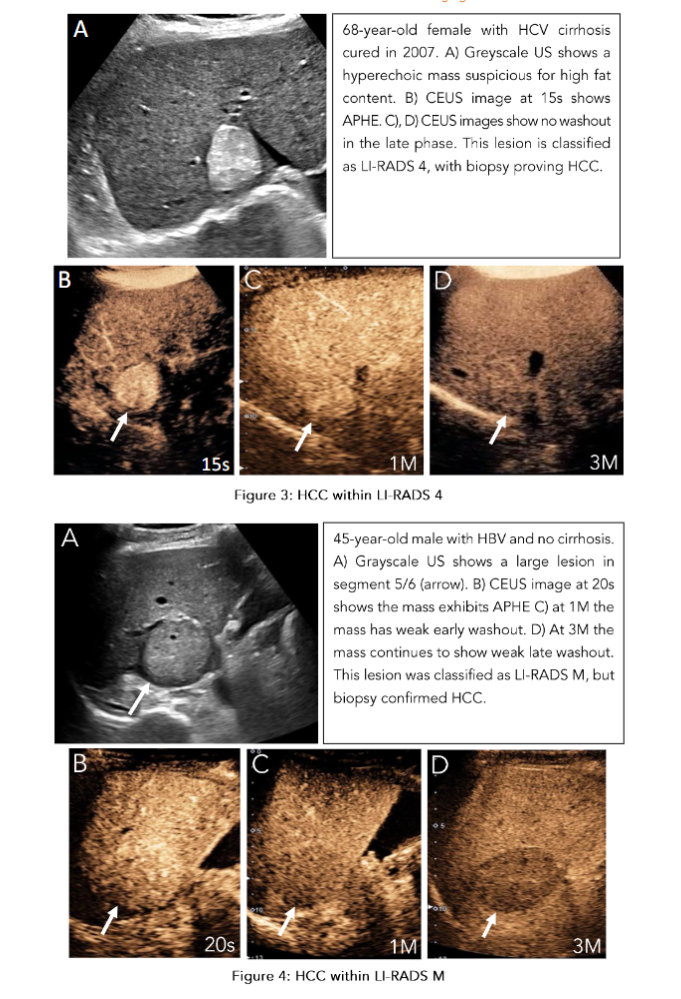

These pseudolesions can be evaluated with US as a problem-solving tool to determine the presence of a true nodule and then characterize its enhancement and washout pattern(20). When we consider lesions that are “probably HCC” (LI-RADS 4), a biopsy is warranted as the incidence of HCC has been shown to be 48% in a study of 175 nodules (Figure 3)(18). This threshold to biopsy is informed by the specificity of the LI-RADS 5 criteria, which is supported by a meta-analysis of fourteen studies showing a pooled per-observation specificity of 91% (95% CI, 89%–93%)(21). Another important category to consider is LI-RADS M (malignancy), which describes a lesion to be “probably or definitely malignant,” but not necessarily in keeping with HCC(16). These lesions may exhibit a characteristic rim of APHE or early washout (less than 1 minute) or marked washout within 2 minutes. Any of these features will classify the lesion as LI-RADS M. Pathologies within this category can include metastases, intrahepatic cholangiocarcinoma (ICC), or in a minority of cases, benign lesions. The prospective identification of metastases or ICC, the second most common malignancy found in patients with chronic liver disease, is of the utmost importance as management strategies and prognosis differ between these pathologies and HCC(22). Alongside these non-HCC lesions, pathological correlation has interestingly shown 28.2% (95% CI, 23.8%–33.1%) of LI-RADS M lesions to ultimately be HCC (Figure 4). This is in part due to the stringent criteria set forth for a LI-RADS 5 lesion and the considerably higher incidence of HCC compared to pathologies like ICC(23). Overall, LI-RADS has been shown to be an effective framework for risk stratifying hepatic lesions concerning for increased risk of HCC.

Figure 2: Resolution of Indeterminate MRI